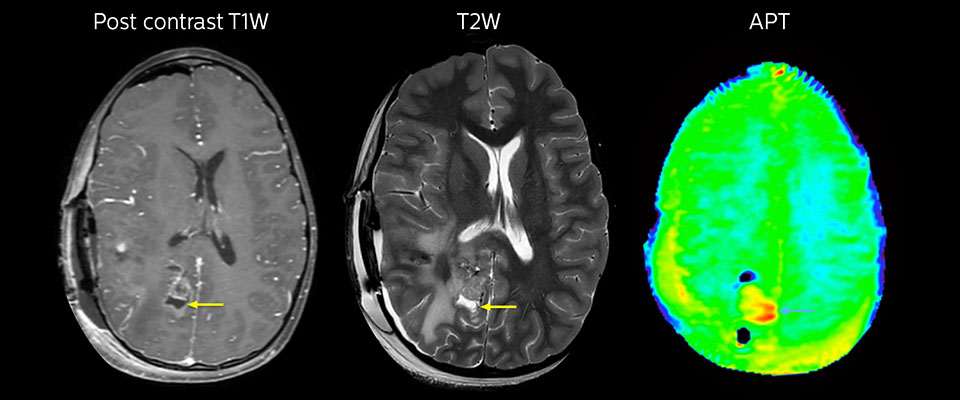

MRT mit APT nach der Resektion

Unmittelbar nach der Resektion wurde erneut eine MRT durchgeführt. Die T2-gewichteten und kontrastverstärkten T1-gewichteten Bilder lassen keine eindeutige Unterscheidung von Residualtumorgewebe und postoperativen Gewebeveränderungen zu. Auf dem APT-Bild ist noch ein hohes Signal zu sehen, das auf Residualtumorgewebe hindeuten würde.